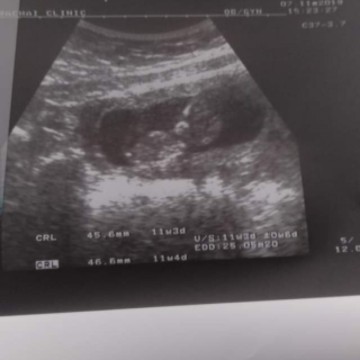

11 สัปดาห์เห็นขนาดนี้แล้วหรือตื่นเต้นจัง อีก 5 สัปดาห์คุณหมอบอกว่ารู้ผลแล้วนะว่าเป็นเพศอะไร